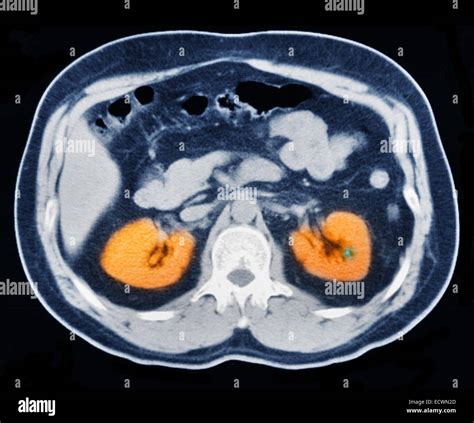

- Tomografia computerizată (CT) a abdomenului și pelvisului, efectuată fără substanță de contrast, este studiul de elecție. Aceasta oferă informații precise despre dimensiunea, densitatea și localizarea pietrei, precum și despre gradul de obstrucție (hidronefroză).

- Ecografia abdomino-pelviană este o metodă sigură, reproductibilă, ieftină, neinvazivă, cu sensibilitate şi specificitate ridicate (95%); poate evidenţia prezenţa calculilor (inclusiv radiotransparenţi), răsunetul asupra căilor urinare (ureterohidronefroza), dar în aproximativ 30% dintre cazuri poate să nu evidenţieze calculii (în special calculi cu diametrul sub 5 mm).